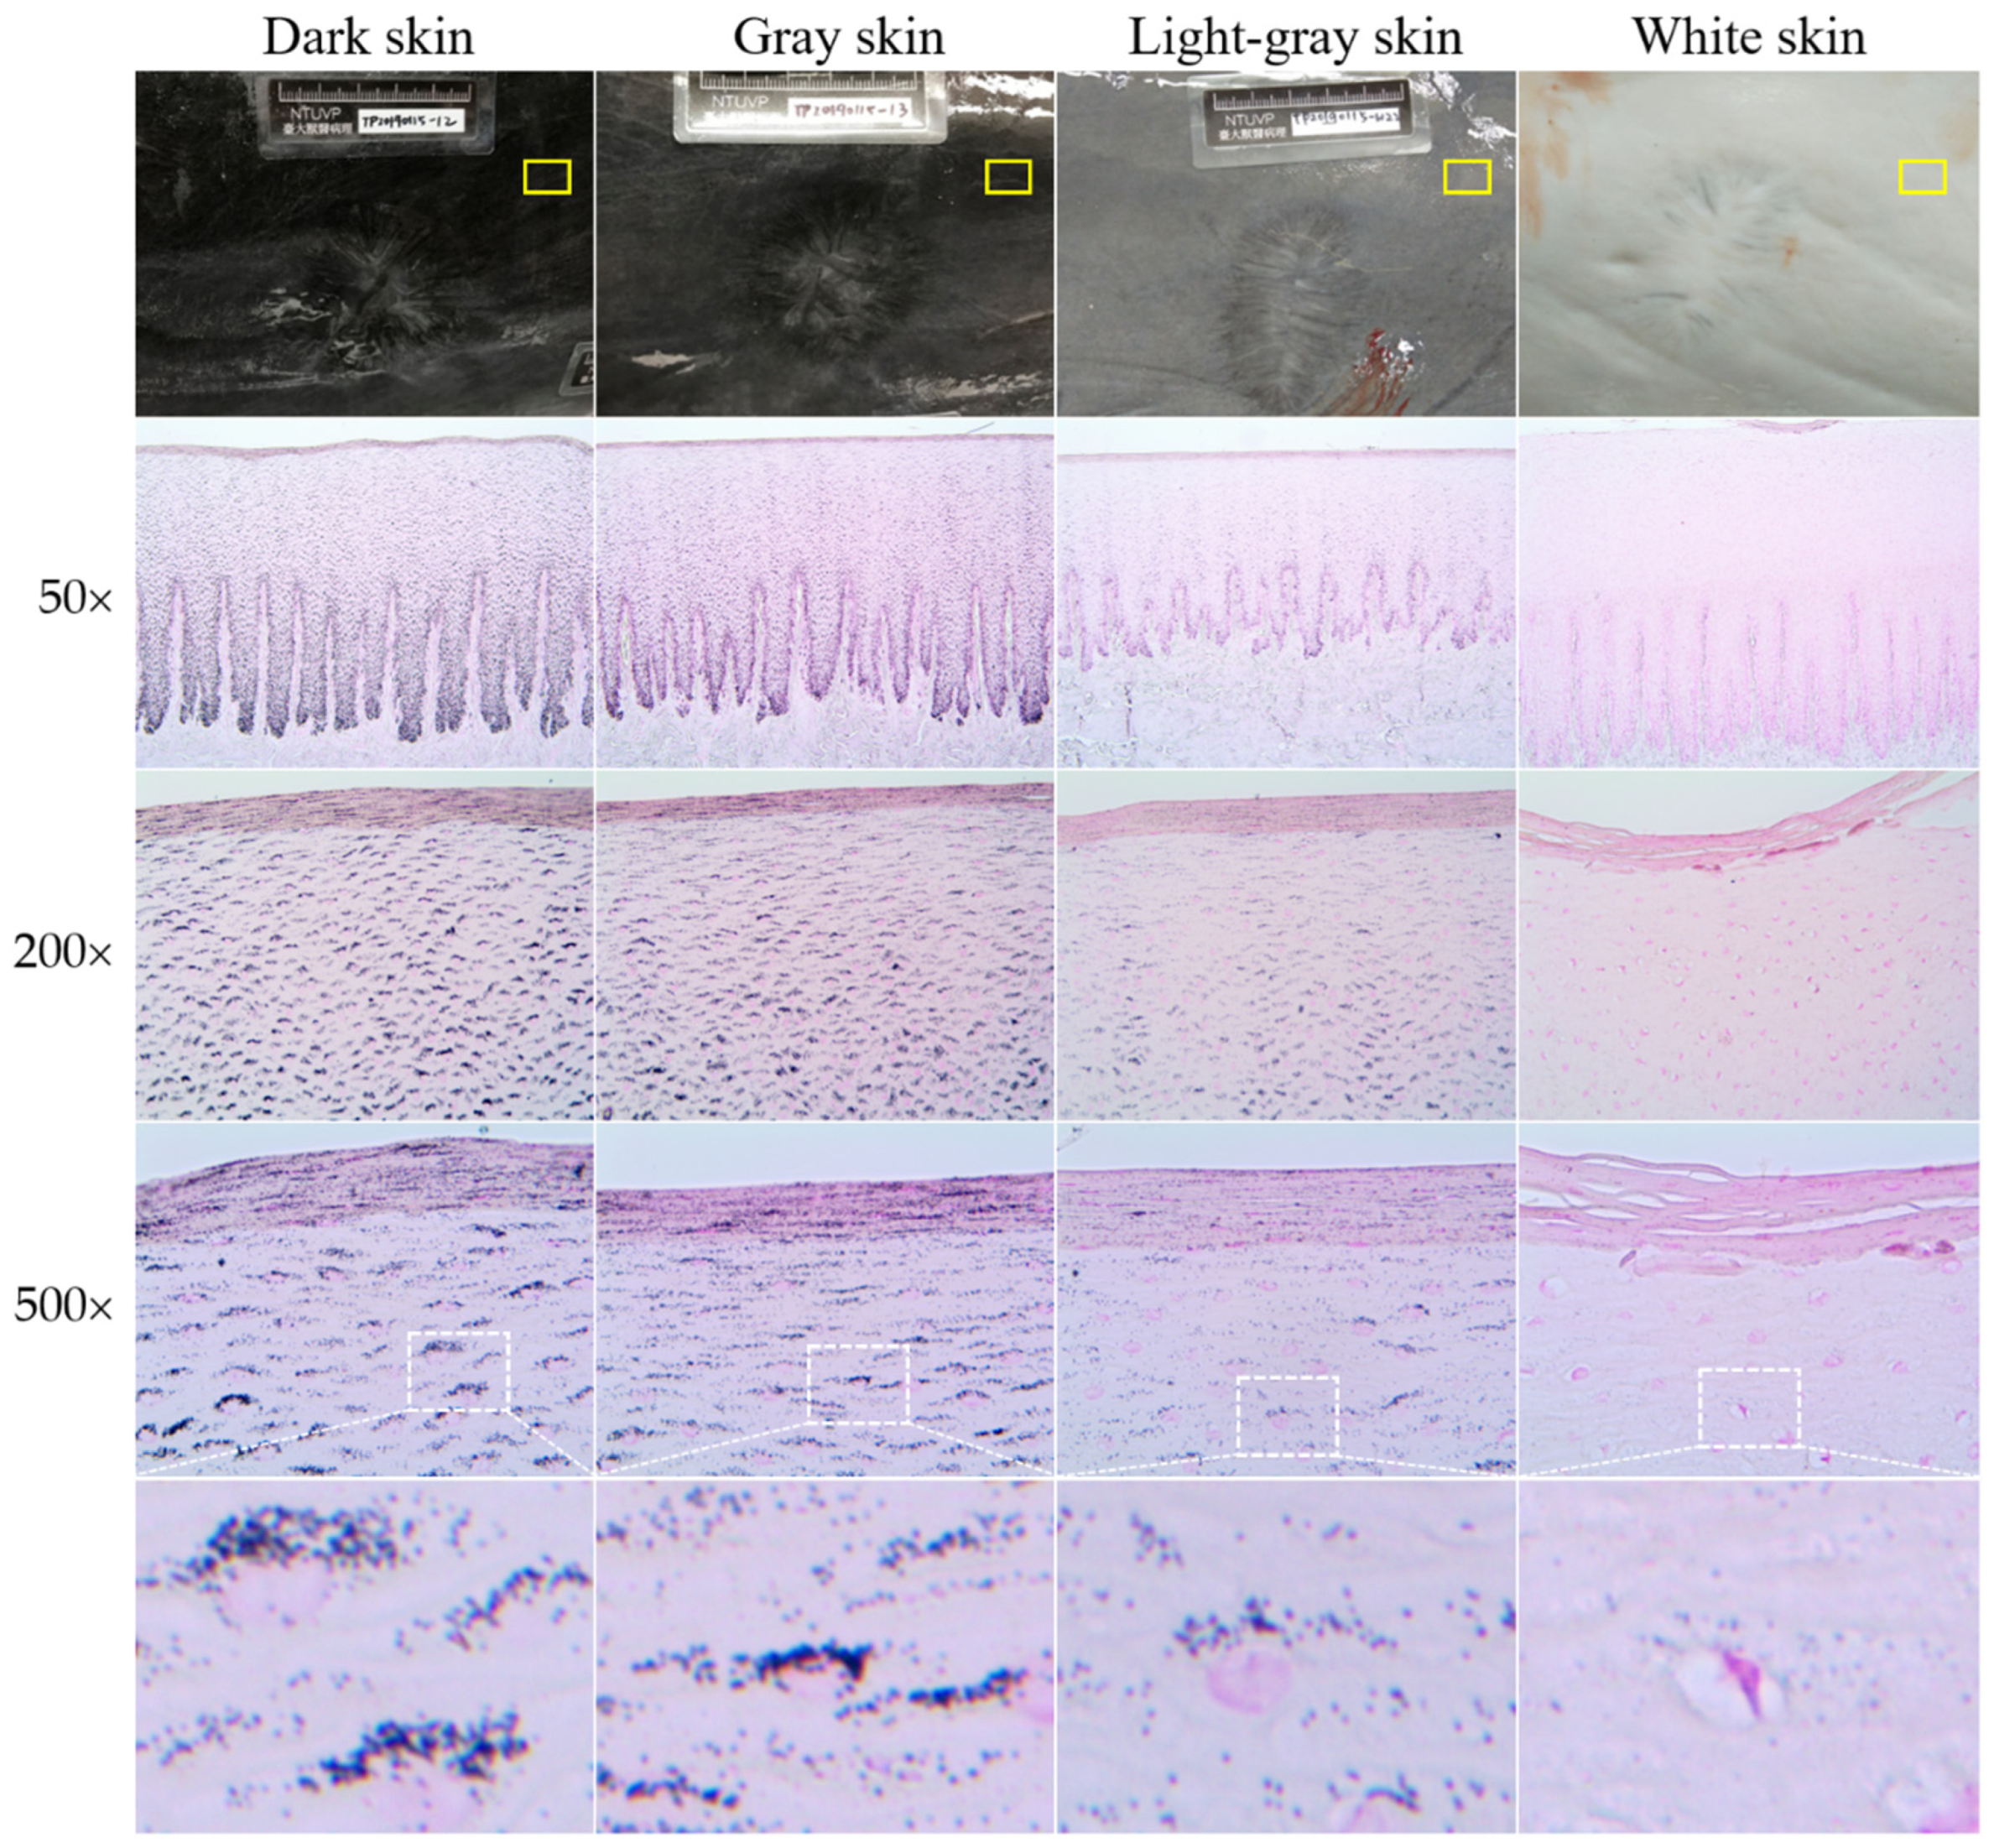

3.1. Fontana–Masson Staining

3.2. Immunofluorescence Staining